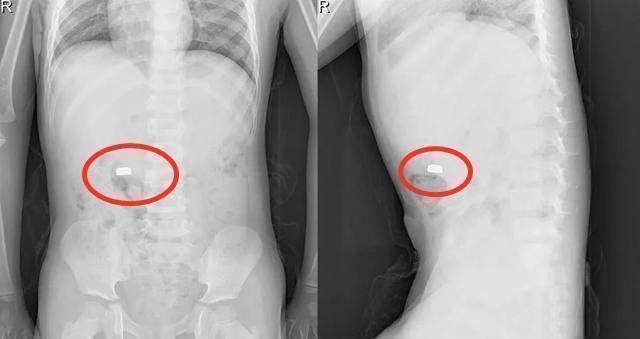

宝妈听完后一身冷汗,连忙拿起玩具一看,果然缺少了一颗电池,于是抱起儿子直奔医院。经医生检查之后,在小孩的肚子里面发现了一颗纽扣电池,还好赵女士送医及时,经过医生的抢救,小孩脱离了危险。